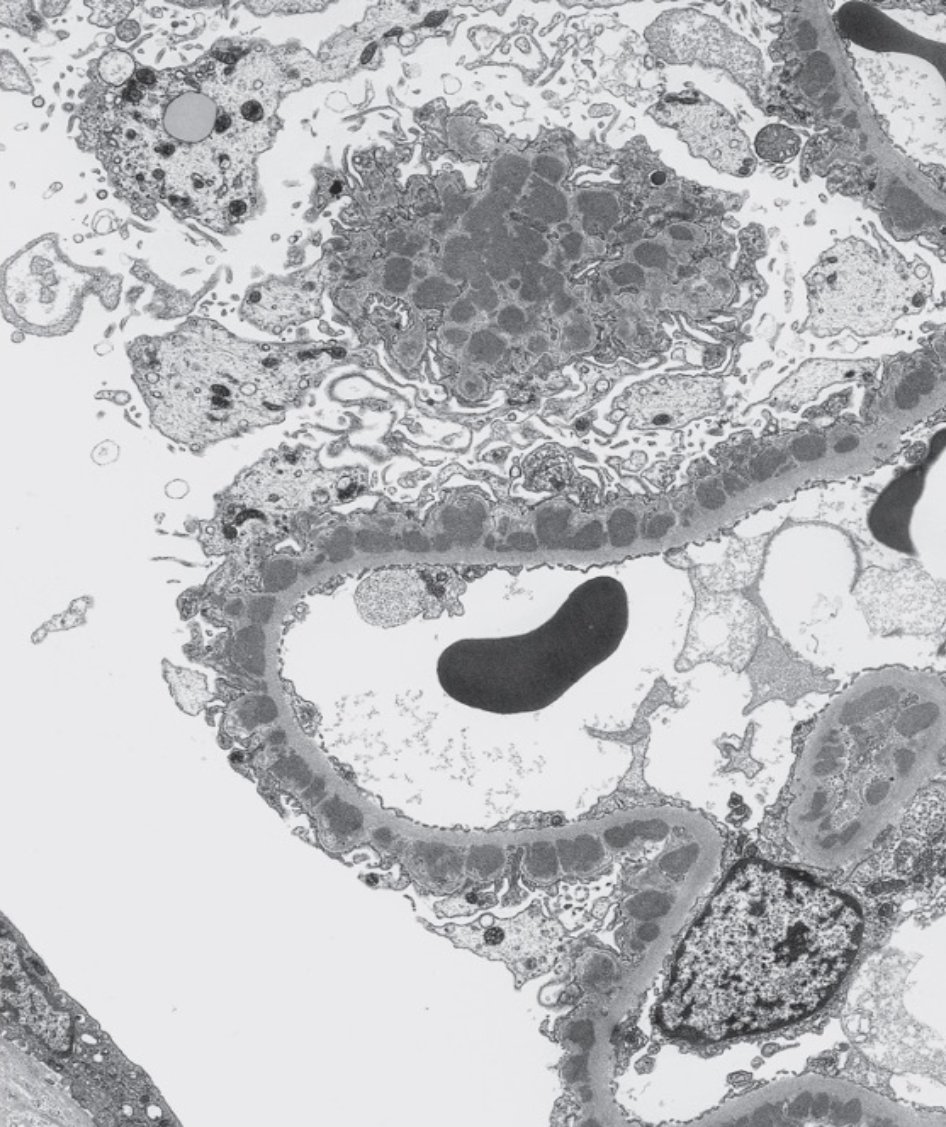

🔬 La microscopía electrónica es clave en biopsia renal. En ~20% de los casos es imprescindible para un diagnóstico final.Aunque a veces se prescinde si LM o IF son concluyentes, esto puede llevar a diagnósticos erróneos o incompletos. No es un lujo, es diagnóstico.

🔬 La microscopía electrónica es clave en biopsia renal.

En ~20% de los casos es imprescindible para un diagnóstico final.Aunque a veces se prescinde si LM o IF son concluyentes, esto puede llevar a diagnósticos erróneos o incompletos.

No es un lujo, es diagnóstico.